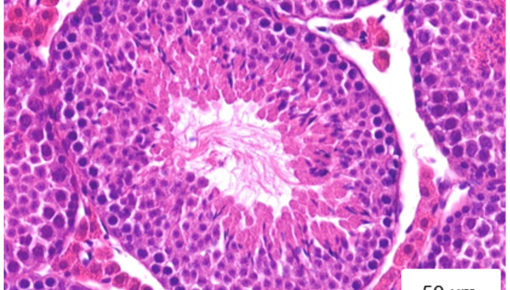

Prenatally in humans and perinatally in mice milestones of ovarian development as critical as the formation of the female’s pool of gametes take place. The gametes and the surrounding specialized stromal cells form the follicles, responsible for ovulation and a main source of sex hormones during the female reproductive life. Importantly, fine-tuned immune responses critically support normal folliculogenesis, ovulation and corpus luteum formation and regression. For example, ovarian macrophages regulate discrete remodelling and vascularization processes that ensure the access of follicles to nutrients and steroid substrates and the egress of hormones into the circulation.